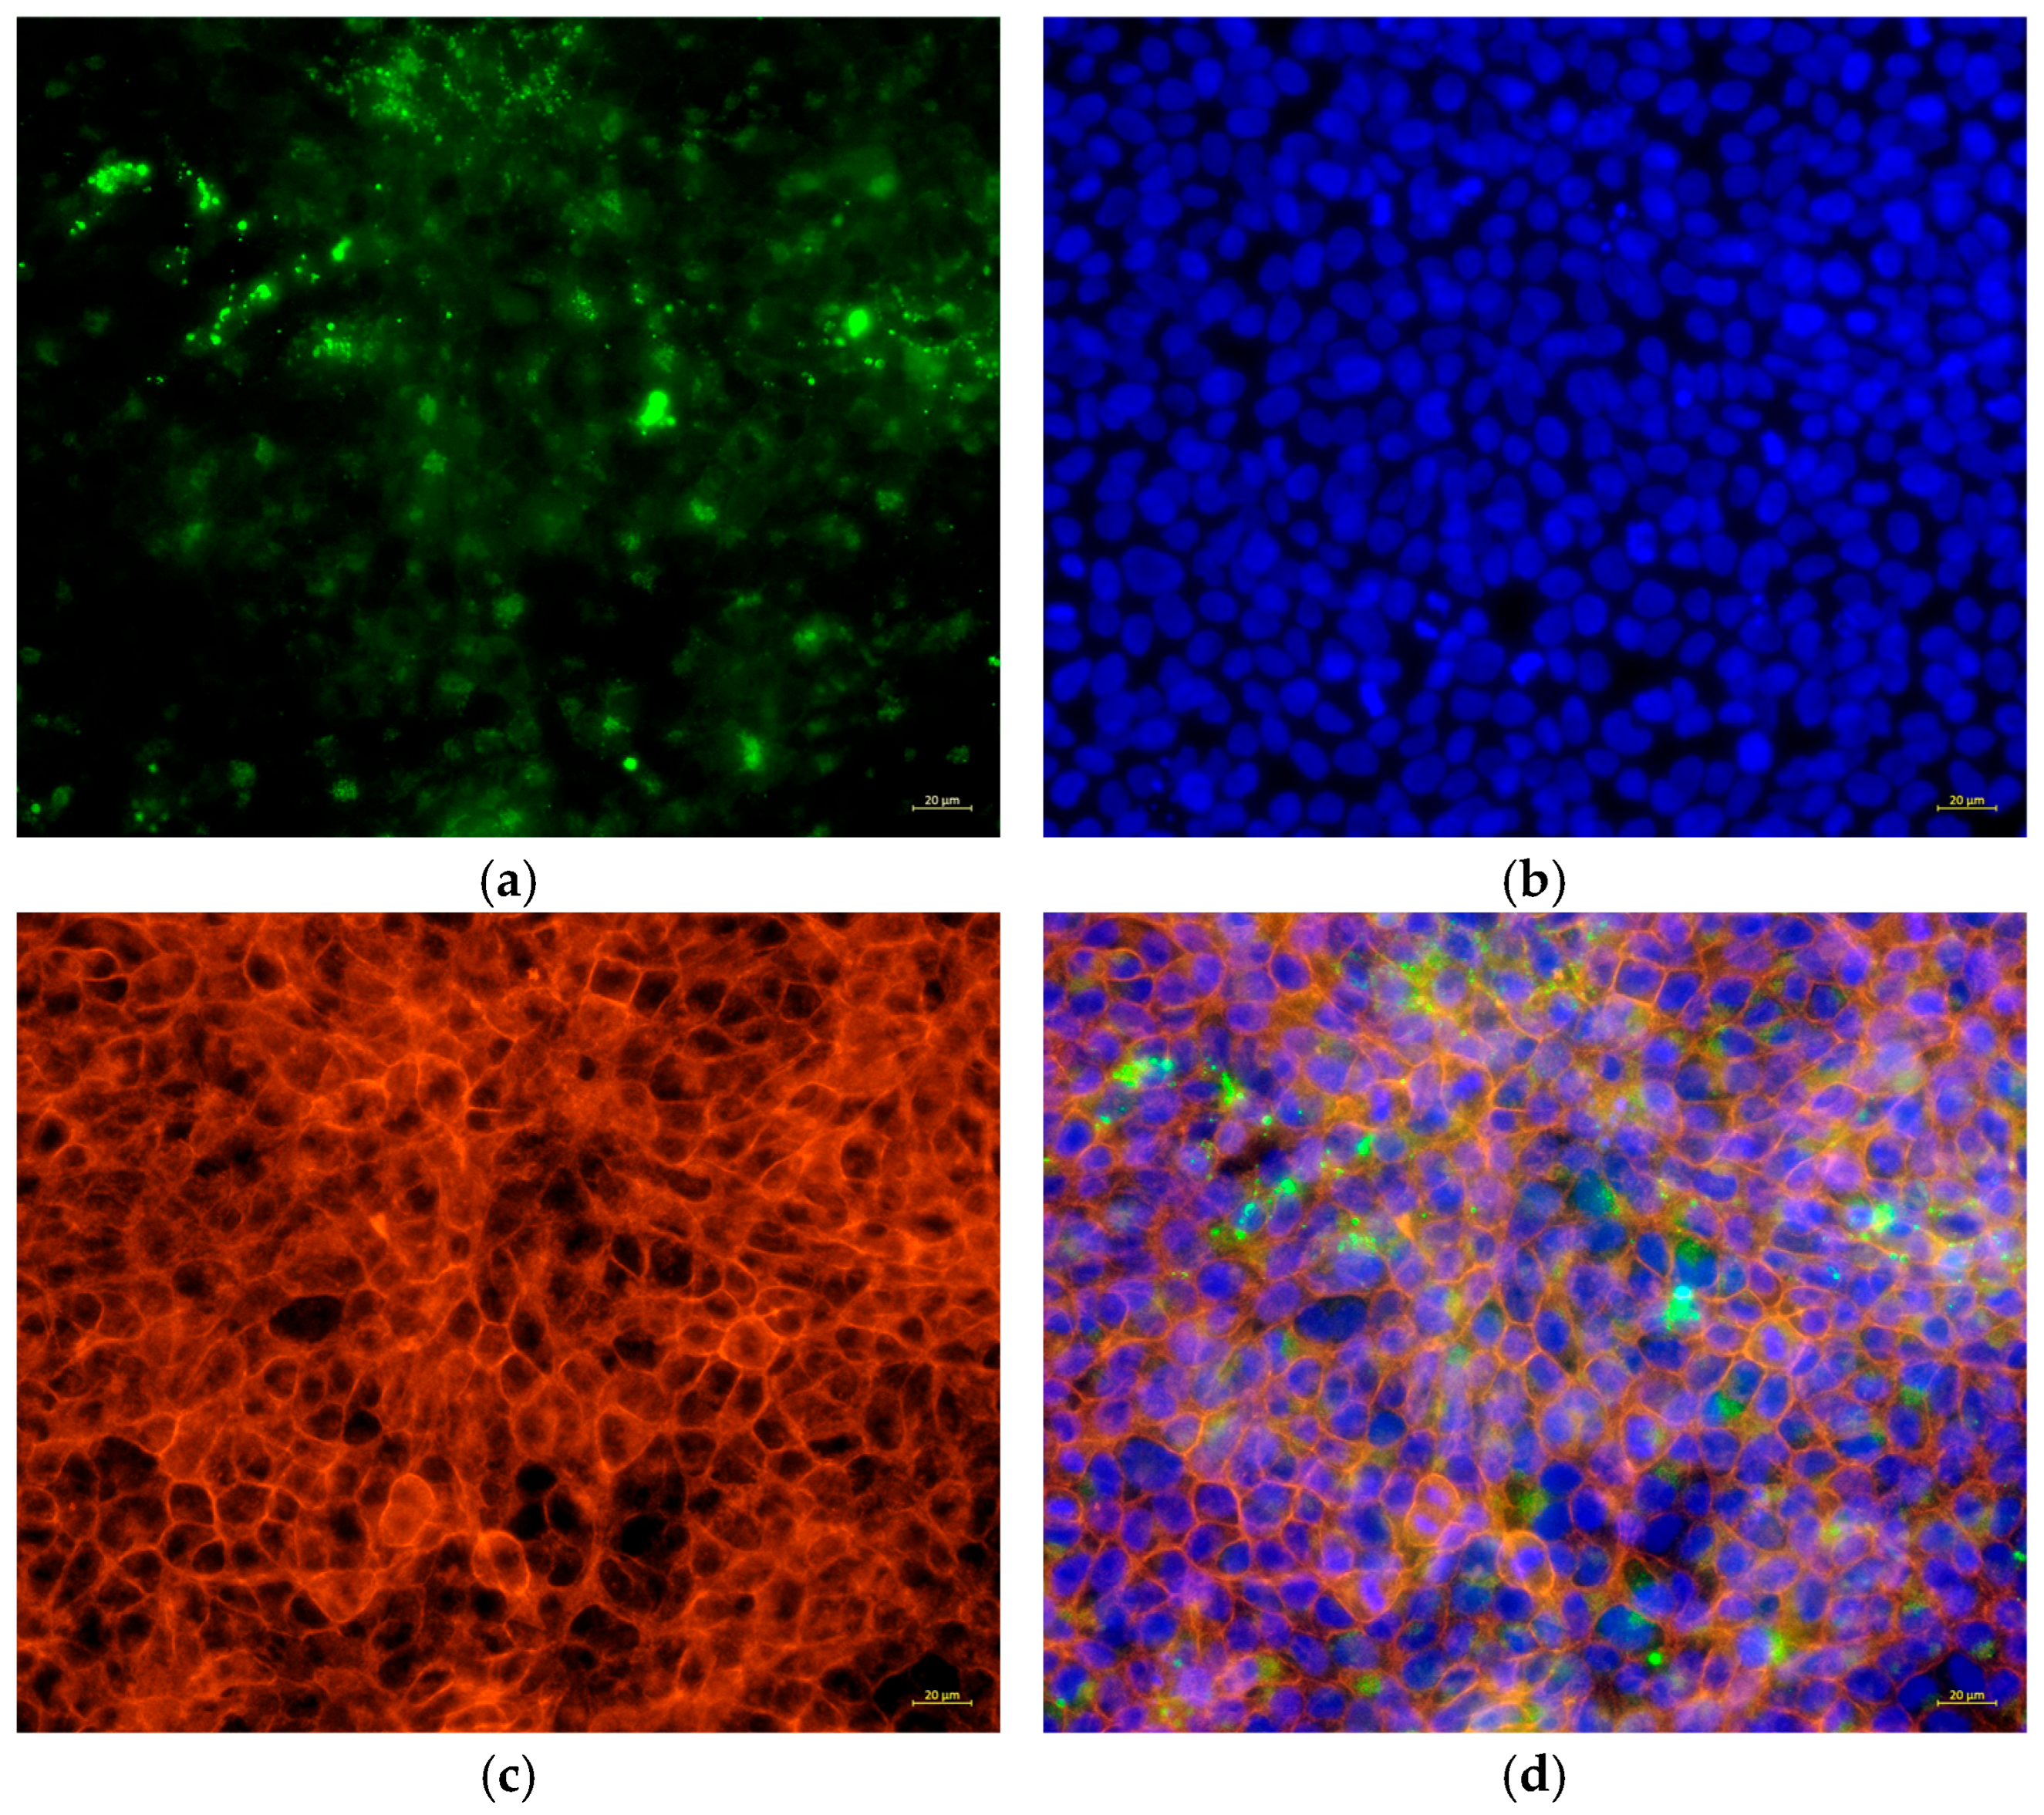

2.13. Bacterial Cell Tracing

To analyze the presence of bacteria, C. acnes IA1 (CICC 10864) was stained with CytoTrace™ UltraGreen (AAT Bioquest, Pleasanton, CA, USA) in accordance with the manufacturer’s instructions. In brief, the bacterial cells were treated with CytoTrace™ UltraGreen for 30 min at 37 °C and then added to HaCaT cells at an MOI of 100:1 for 24 h. Then, the floating bacteria were removed by washing 3 times with PBS. The cells were fixed on ice with a 4% formaldehyde solution in PBS for 15 min and then permeabilized with 0.5% Triton X-100 in PBS for 10 min at room temperature. Subsequently, the cells were stained by Phalloidin-AF594 (Cohesion Biosciences, London, UK) for 20 min, followed by Hoechst 33342 (Beyotime Biotechnology) for 5 min according to the manufacturer’s instructions. The samples were observed by using ZEISS Axiovert 5 fluorescence microscopy (ZEISS, Jena, Germany).

Table 5). Fluorescence microscopy revealed biofilm formation by

C. acnes IA

1 on keratinocyte surfaces, supporting its role in persistent infection and chronic inflammation [

10]. The significant increase in IL-6 secretion validates the transcriptomic upregulation of IL-6 signaling and aligns with hub gene functions, as HNRNPA2B1 and RBM39 regulate cytokine expression through splicing [